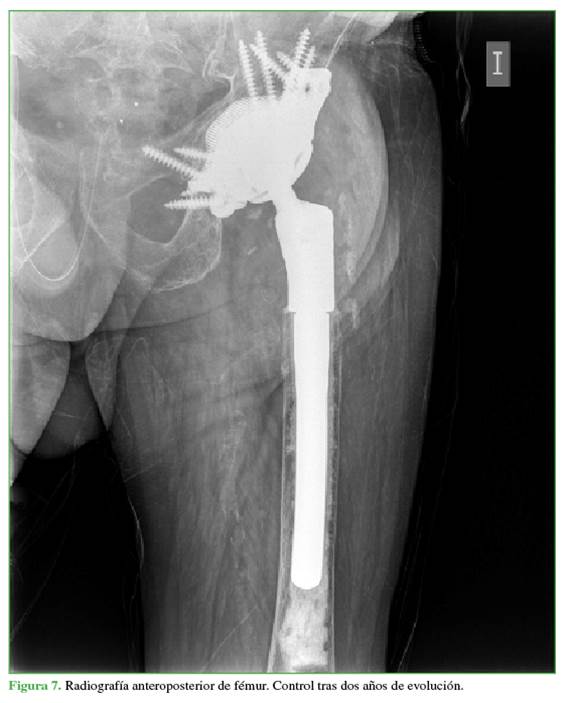

En el último control clínico (a los dos años de la última operación), la evolución del paciente era satisfactoria (Figura 7). El balance articular era correcto, sin dismetrías notificadas. El puntaje de la prueba de Barthel5 era de 80; no sufría dolor, excepto tras la deambulación excesiva (más de 1000 m) y deambulaba con un bastón. Las radiografías de control no revelaron aflojamiento ni hundimiento del material acetabular ni femoral. Por otro lado, en comparación con la cadera contralateral, el centro de rotación estaba recuperado. Tampoco ha tenido lesiones neurovasculares durante la evolución.